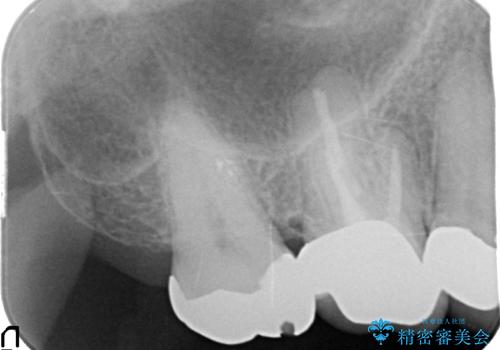

- 右上の奥歯がしみるとのことで確認すると、右上の一番奥の歯の銀歯の下が虫歯になっていました。

かなり大きな銀歯が装着されていたので、かぶせ物にて治療を行うこととなりました。

同時に右上の後ろから3番目の歯のかぶせ物も適合が悪かったので同時に治療することとなりました。